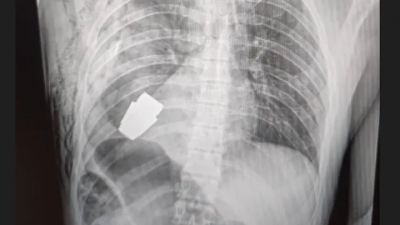

Ουκρανία: Χειροβομβίδα εντοπίστηκε μέσα στο σώμα στρατιώτη - «Θα μπορούσε να εκραγεί ανά πάσα στιγμή» 11/01/2023 - 12:13 - Διεθνή